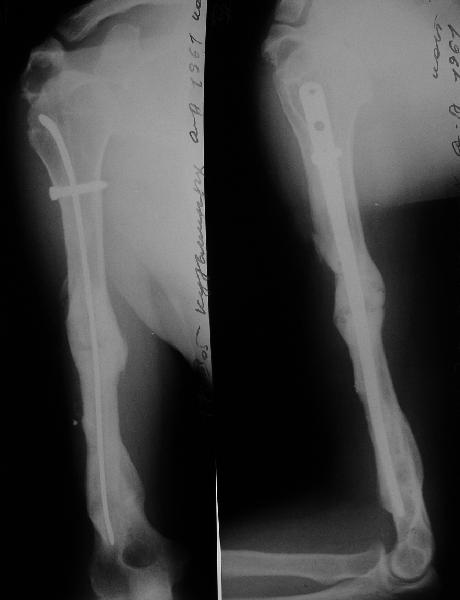

Такие надмыщелковые переломы в изолированном виде у нас в последние годы обычно фиксируются плоским титановым стержнем a la Зверев-Ключевский антеградно. Но тут еще и вышележащие проблемы.

Наверно, можно пойти на укорочение, убрав металлический цилиндр, не такой уж большой дефект. Снимки в чем-то похожего пациента прилагаю - тоже несращение диафиза после многократных операций, и надмыщелковый свежий перелом (случился после удаления обломка стержня аппарата).

В данном случае переверните стержень и добавьте пластину, второй проекции я, что-то не увидел, но думаю самую дешевую бу треть трубки. Привет ЛАФ.